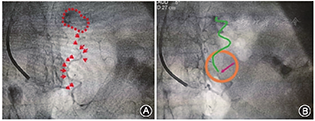

入院后予以阿司匹林肠溶片(100 mg,顿服),硝苯地平控释片(60 mg,顿服),二甲双胍缓释片(0.5 g,2次/d),米格列醇(50 mg,3次/d),阿托伐他汀钙片(20 mg, 2次/d),氯化钾缓释片(1 g, 3次/d),螺内酯(20 mg, 2次/d)(肾上腺采血后开始服用)等治疗,患者血压波动于170/110 mmHg左右,血钾3.2 mmol/L。患者左侧醛固酮瘤诊断明确,根据2020年原发性醛固酮增多症诊断治疗的专家共识,建议行腹腔镜下肿瘤切除术,由于患者拒绝外科手术治疗,经与患者充分沟通后,患者接受了经皮超选择性肾上腺动脉栓塞术(transcatheter adrenal arterial embolization,TAAE)。手术过程见图3。